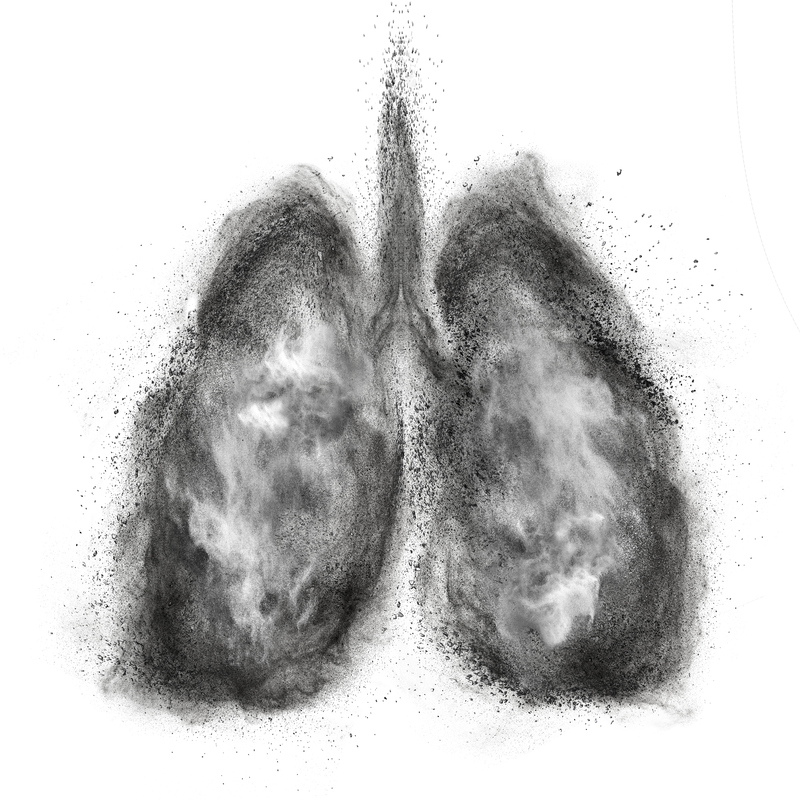

痰多又咳不太出來怎麼辦?醫師教你排痰3要訣

春天晝夜溫差大,是呼吸道疾病高峰。當有呼吸道不適,難免會出現痰多症狀,到底痰多又咳不太出來時,該怎麼辦?

老菸槍、慢性支氣管炎、肺氣腫的患者,因纖毛被破壞,無法有效擺動,會一直處於痰多狀態。而慢性支氣管擴張的患者,最常見的原因是由於肺炎導致支氣管變形扭曲,加上不健康的纖毛運動,無法順利排出痰液。另一種情況是季節交換,當有呼吸道敏感、病菌感染時,纖毛的擺動可能沒有大問題,但會因病菌、壞死細胞增加,使得痰液的量增加、變得濃稠時,也會出現痰多的症狀。

當越來越多的痰液,逐漸堆積在氣管、支氣管、肺泡會讓呼吸道變狹窄,若合併有發燒時,痰液有可能因水分減少而變得更濃稠,不易咳出來。蓄積的痰液,就有如病菌的培養皿,引起感染造成肺炎,甚至會影響肺臟的氣體交換功能,出現呼吸困難的不適。